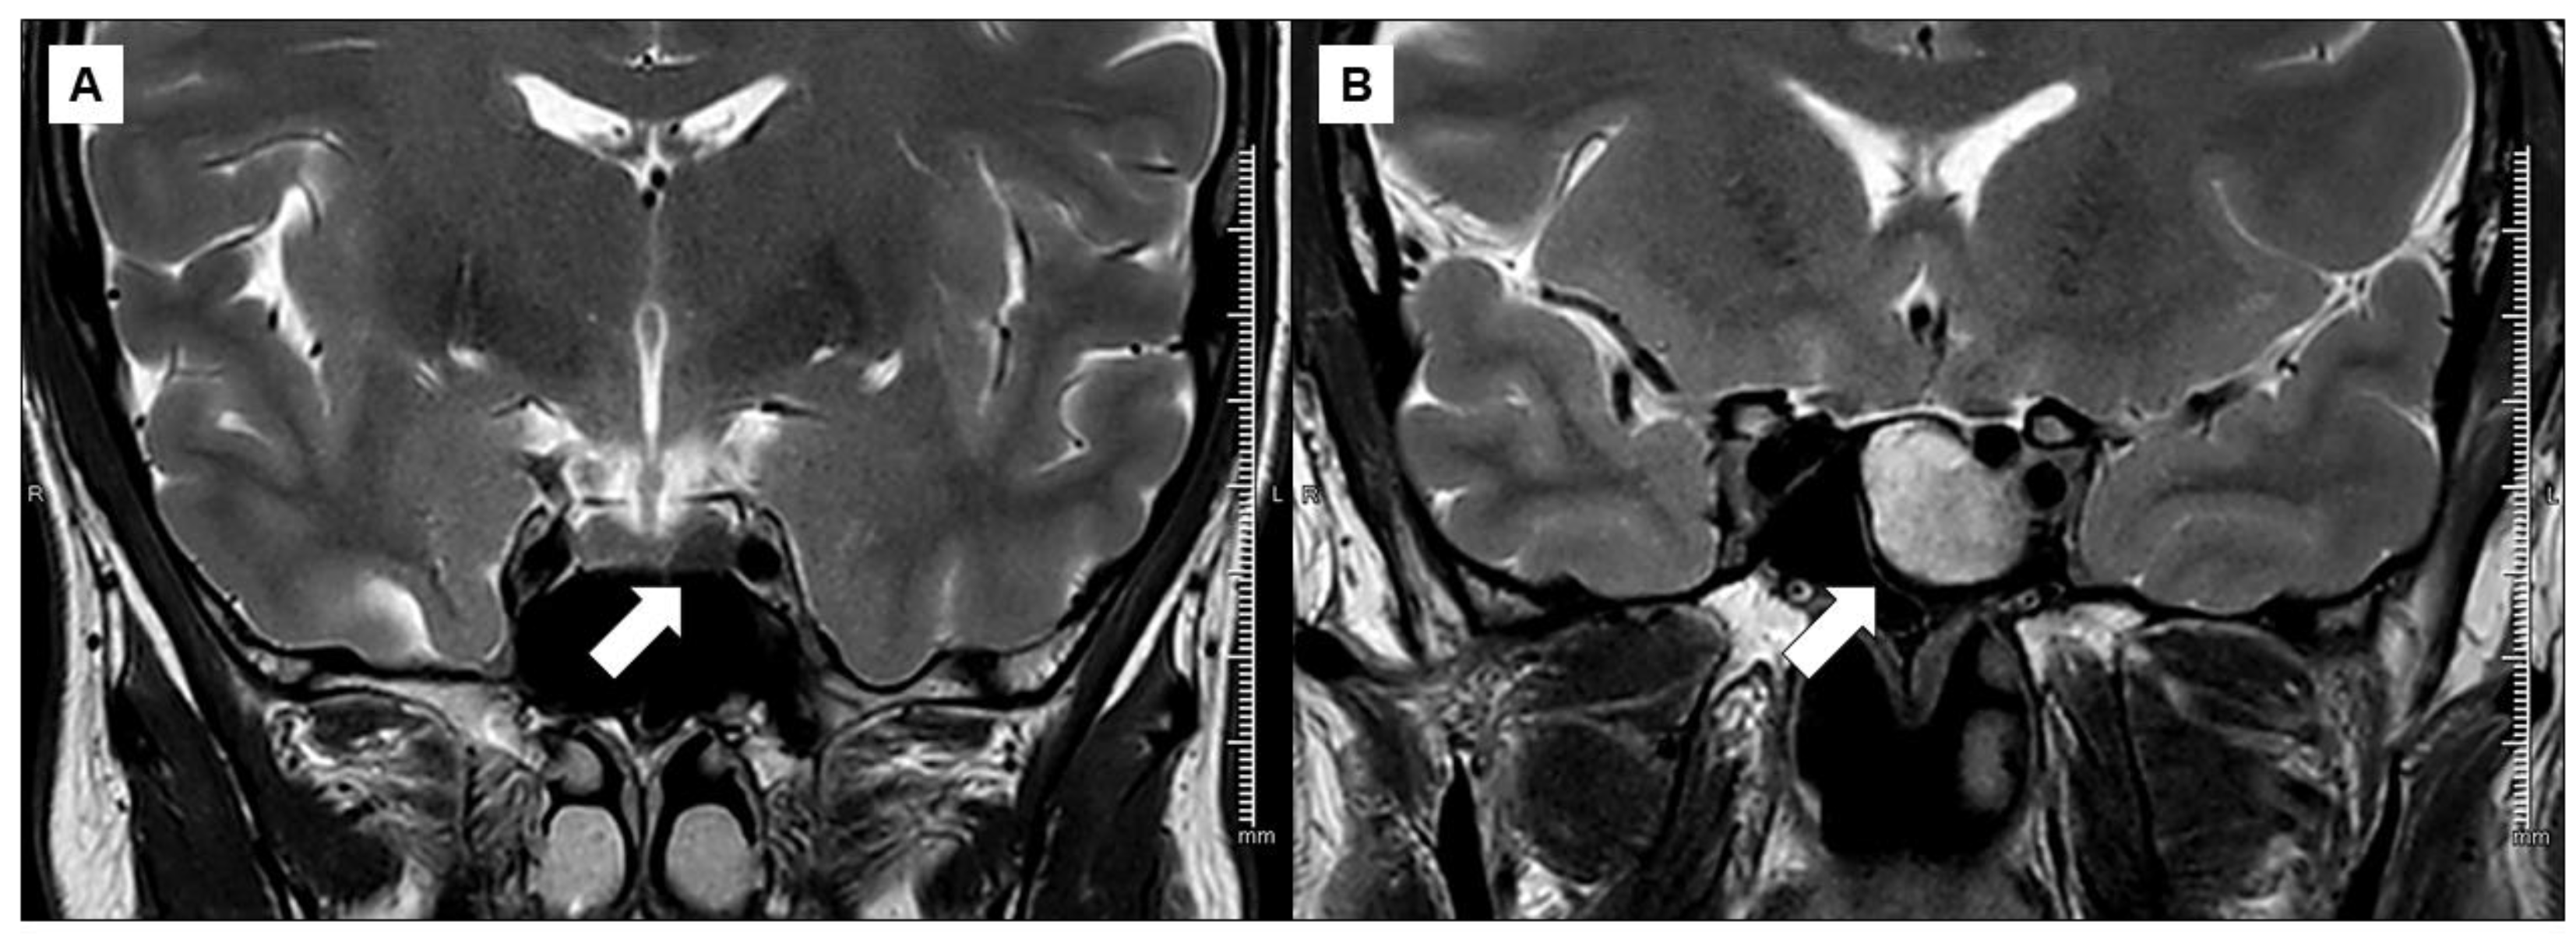

| 73, 76 | T2-iso/hyper-intensity (n, %) | 49, 67.1 | 39, 75 | 10, 47.6 | 0.048 |

| T2-iso/hyper-intensity | 73, 76% (52 R-SRL, 21 S-SRL) | 1.19 | 3.3 (1.14–9.54) | 0.027 | 0.64 (0.52–0.75) |